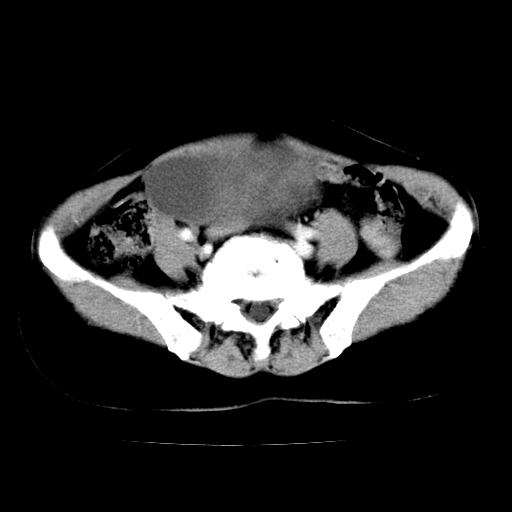

标题: CT24785:女,62岁,发现下腹部肿物半年。 [打印本页]

标题: CT24785:女,62岁,发现下腹部肿物半年。

女,62岁,发现下腹部肿物半年,下腹部不适。

考虑子宫平滑肌肉瘤可能性大。

实性成分太多,要是囊腺瘤也要考虑恶性。